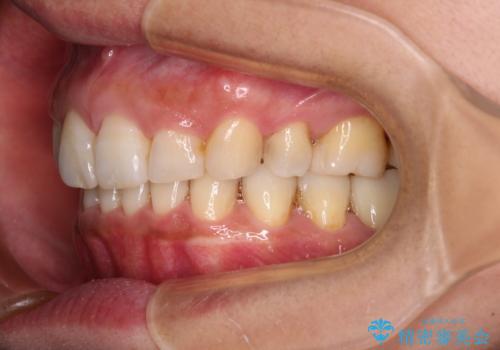

- 以前行った抜歯矯正が後戻りし、開いてしまったスペースが気になるとのことで来院された患者様です。

インビザラインを用いて開いてしまったスペースと前歯のデコボコを改善することとしました。

矯正治療後には気になっていた銀歯をセラミッククラウンやセラミックインレーにて治療することとしました。

上顎前歯を左右対称となるように歯列を整えたいとのことでしたが、すり減って形態が大きく異なっていたため、できる範囲での仕上がりとなりました。